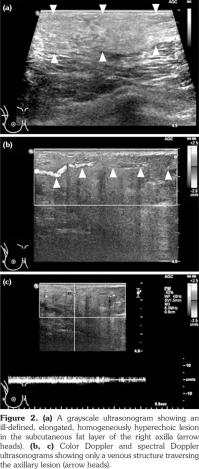

Full-field digital mammography was performed (MAMMOMAT Inspiration; Siemens AG, Munich, Germany). A right mediolateral oblique view revealed an asymmetric density in the right axilla (Figure 1). Ultrasonography was performed with a 5- to 12-MHz linear transducer (iU22; Philips Medical Systems, Bothell, WA, USA), which identified a poorly defined, elongated, homogeneously hyperechoic lesion in the subcutaneous fat layer of the right axilla (Figure 2). The lesion did not exhibit increased vascularity, except for a normal traversing venous structure (Figure 2). The lesion was surgically excised. Pathological examination confirmed the diagnosis as lipogranuloma (Figure 3). On the other hand, complete blood test results were normal.

Histopathologically, lipogranuloma is characterized by multiple fat vacuoles surrounded by granulomatous tissue composed of multinucleated giant cells, epithelioid histiocytes, and fibrosis.(2,6) Regardless of the kind of exogenous material responsible for secondary lipogranuloma including paraffin, petrolatum, mineral oils, lanolin, and silicone, a similar histopathological appearance is produced after injection.(6)